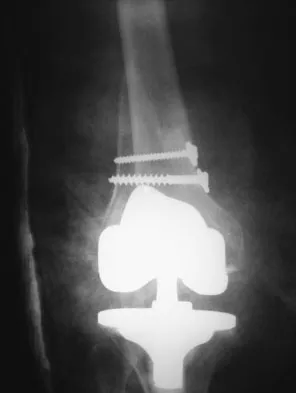

Transform Your Joints: Techniques to help to reduce arthritis discomfort

This topic focuses on Transform Your Joints: Techniques to help to reduce arthritis discomfort, Managing arthritis symptoms and improving joint health involves key strategies. Regular low-impact exercise like swimming or walking, along with stretching, can help to reduce pain and stiffness. Maintaining a healthy weight, practicing good posture, and wearing proper footwear also help. Eating an anti-inflammatory diet rich in omega-3s, fruits, and vegetables can further help to reduce inflammation, as can heat or cold therapy.